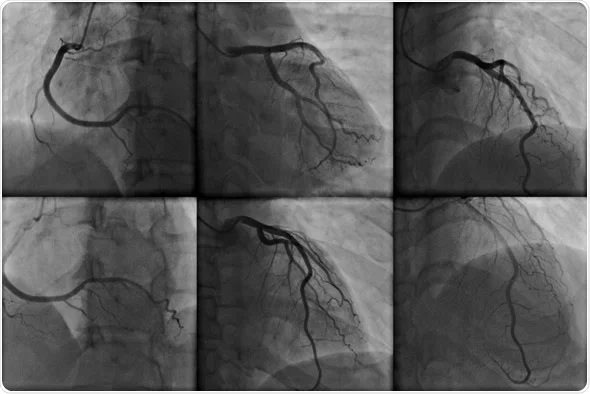

آنژیوگرافی قلب یکی از دقیق‌ترین و کاربردی‌ترین روش‌های پزشکی است که برای بررسی عروق کرونری و تشخیص مشکلات مرتبط با جریان خون به قلب انجام می‌شود. در این روش، پزشک یک کاتتر بسیار نازک را از طریق شریان‌های بدن، معمولاً از کشاله ران یا مچ دست، وارد سیستم عروقی بیمار می‌کند. سپس با تزریق یک ماده رنگی خاص که در تصاویر اشعه ایکس دیده می‌شود، تصاویر دقیقی از عروق کرونری قلب گرفته می‌شود. این تصاویر کمک می‌کنند تا پزشک بتواند نقاطی از عروق که ممکن است دچار انسداد یا تنگی شده باشند را تشخیص دهد و برای درمان آن‌ها برنامه‌ریزی کند. علاوه بر این، در برخی موارد خاص، آنژیوگرافی می‌تواند بلافاصله پس از تشخیص، به درمان نیز منجر شود، مانند باز کردن عروق با استفاده از بالون یا استنت‌گذاری.

پس از بی‌حسی، کاتتر نازک و انعطاف‌پذیر از طریق شریان وارد بدن می‌شود و به سمت عروق کرونری هدایت می‌شود. هنگامی که کاتتر در محل مناسب قرار گرفت، ماده رنگی به داخل عروق تزریق می‌شود. این ماده رنگی که در اشعه ایکس قابل مشاهده است، باعث می‌شود که عروق کرونری به وضوح در تصاویر دیده شوند و هرگونه انسداد یا تنگی به سرعت شناسایی شود.